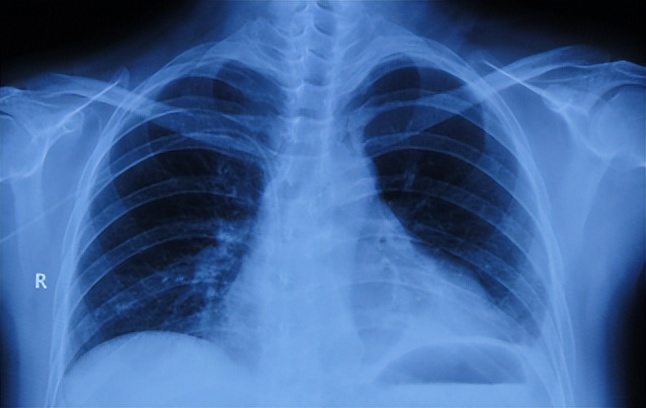

听神经瘤切除术后14天即2013年11月28(腰大池引流术后7天),查肺片(图-4)认为有感染。

图-4:2013年11月28日肺片

听神经瘤术后49天即2014年1月2日,仍间断发热,查肺片(图-9)认为仍有感染。

图-9:2014年1月2日肺片

抗真菌治疗后大约10天后因血钾偏低明显改为大扶康静脉抗真菌治疗。听神经瘤术后73天即2014年1月28日,查肺片(图-11)仍有感染。

图-11:2014年1月28日肺片